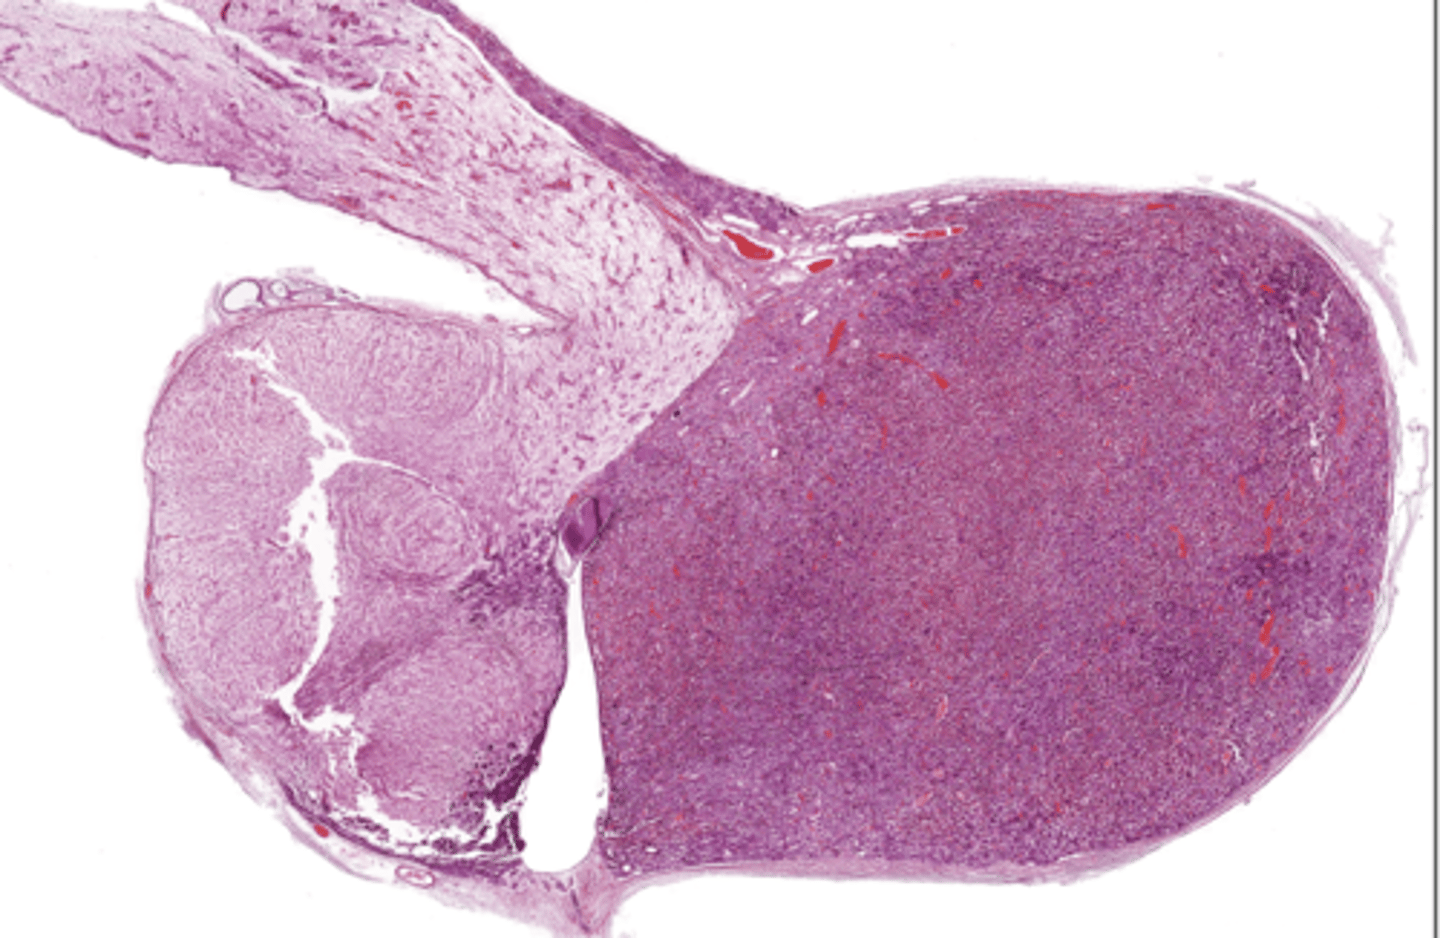

Thymus

Pancreas

Pancreatic islet

Adrenal gland

Adrenal cortex

Zona glomerulosa

Zona fasciculata

Zona reticularis

Adrenal medulla